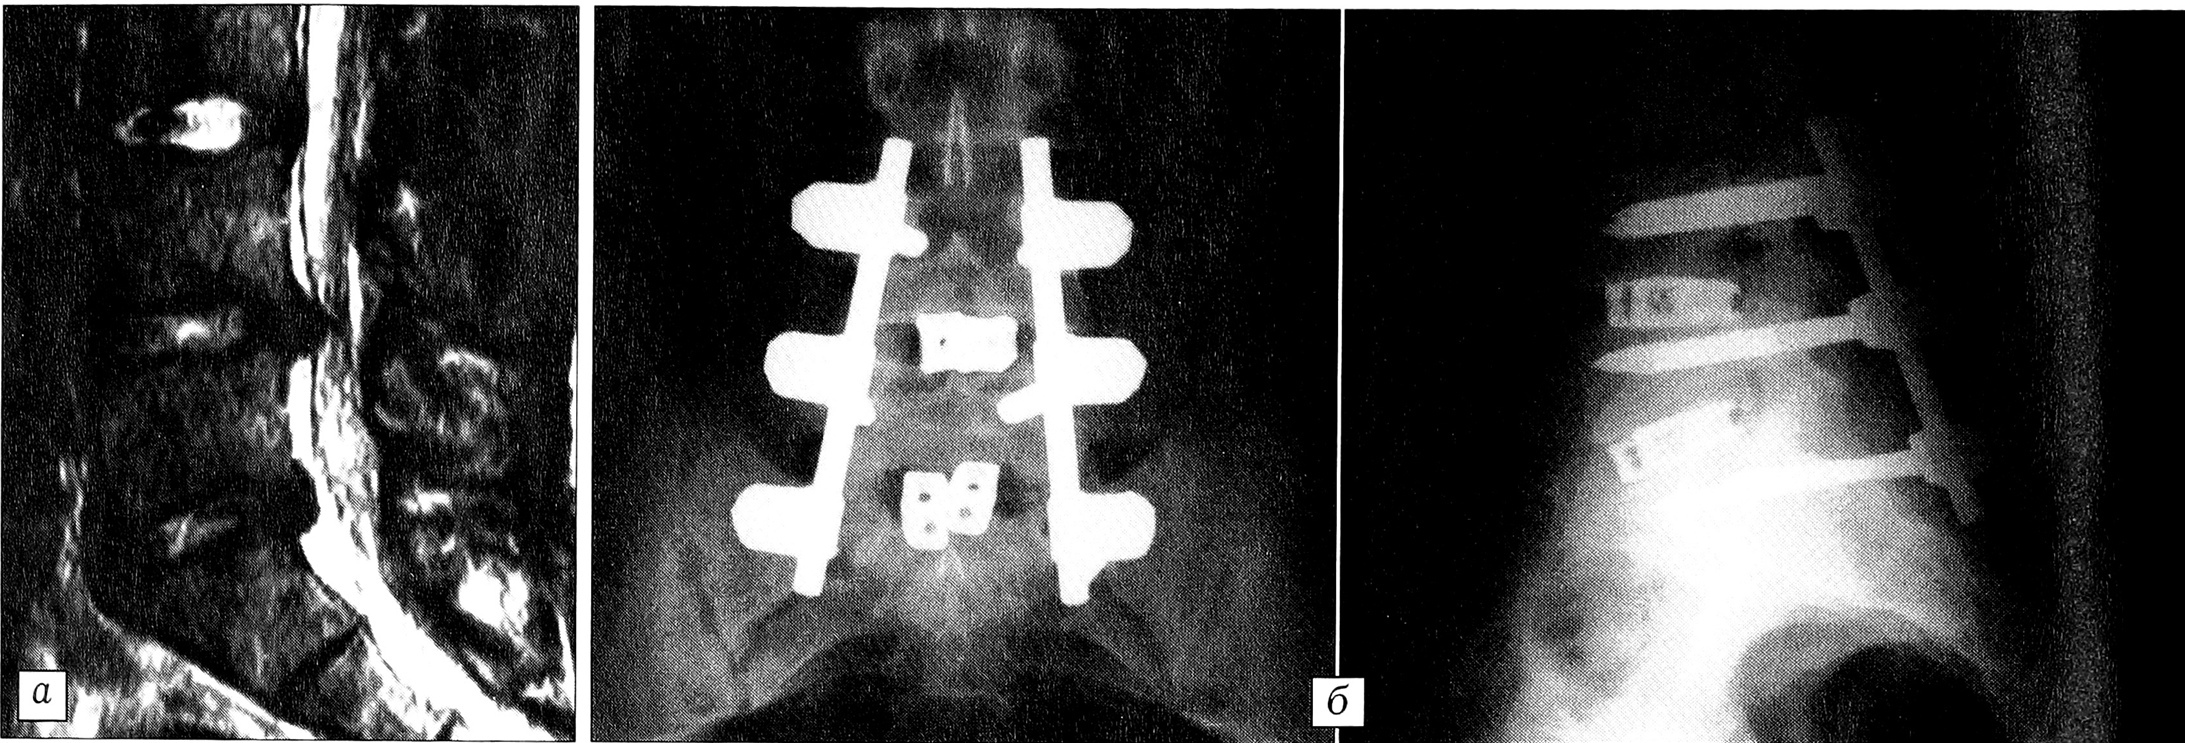

Большинство наших больных поступили с запущенным процессом, длительно леченным консервативно. При магнитно-резонансной томографии выявлены следующие виды поражения диска: протрузия — у 215 больных, экструзия — у 380, секвестрация — у 122 (в том числе внутриканальный секвестр — у 118, внутриоболочечный — у 4). В 96,3% случаев мы обнаружили или значительное выпячивание межпозвонкового диска, вызывающее грубую компрессию корешка, или секвестр (рис. 1), причем у большинства пациентов этот процесс существовал длительное время. Только у 3,7% больных корешковый синдром был вызван небольшой протрузией диска (рис. 2), «подходящей» для применения эндоскопической технологии. У 226 (31,5%) больных имелась сочетанная патология: у 116 — стеноз позвоночного канала (гипертрофия задней продольной, желтых связок), у 38 — спондилолистез I—II степени, у 72 — спаечный процесс (у 49 —вокруг одного корешка, у 19 — внутриканальный, у 4 — внутриоболочечный).

Рис. 1. Секвестрированная грыжа L4-5 (магнитно-резонансная томограмма).

Рис. 2. Небольшая протрузия диска L4-5 (магнитно-резонансная томограмма).

До сих пор остается дискуссионной проблема применения спондилодеза после дискэктомии [17]. Когда мы оперируем пациента с исходно стабильным позвоночным сегментом, спондилодез после микродискэктомии не показан. Однако есть группа больных, у которых до операции выявляются исходная небольшая нестабильность или предрасполагающие к ней изменения в позвоночнике (спондилолиз, spina bifida и т.д.). При выполнении резекции желтой связки и микродискэктомии первичная нестабильность может усугубиться. Кроме того, у молодых пациентов после дискэктомии может произойти уменьшение высоты межпозвонковых промежутков и перегрузка межпозвонковых суставов, что вызовет боли в пояснице в отдаленном периоде. У этих больных приходится, кроме дискэктомии, выполнять стабилизирующие операции одного из трех типов: установка межпозвонковых кейджей с аутокостной крошкой; транспедикулярная фиксация (мы предпочитаем фиксаторы USS /АО/) с межтеловым спондилодезом кейджами с аутокостной крошкой (рис. 3) или материалом cronOS (porous B-tricalcium phosphate granules) фирмы «Mathys»; межтеловой спондилодез аутокостью и фиксатором с термомеханическим эффектом памяти формы, разработанным нашим коллективом [4].

Рис. 3. Больной Н. Диагноз: посттравматические грыжи дисков L4-5, L5-S1.a — магнитно-резонансная томограмма до операции;б — рентгенограммы после операции: произведены микродискэктомия L4-5, L5-S1 с обеих сторон, транспедикулярная фиксация и спондилодез кейджами с аутокостью.